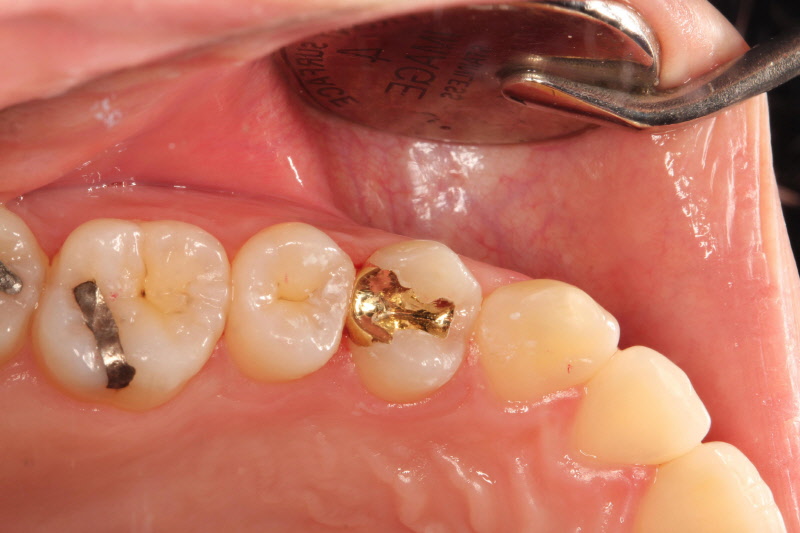

금 인레이